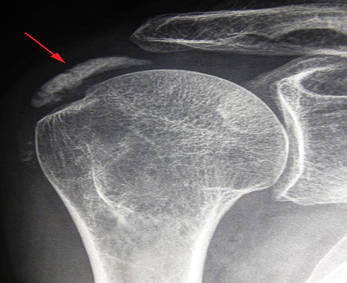

Une calcification des tendons de l’épaule est la formation au sein d’un ou plusieurs tendons d’un dépôt calcique.